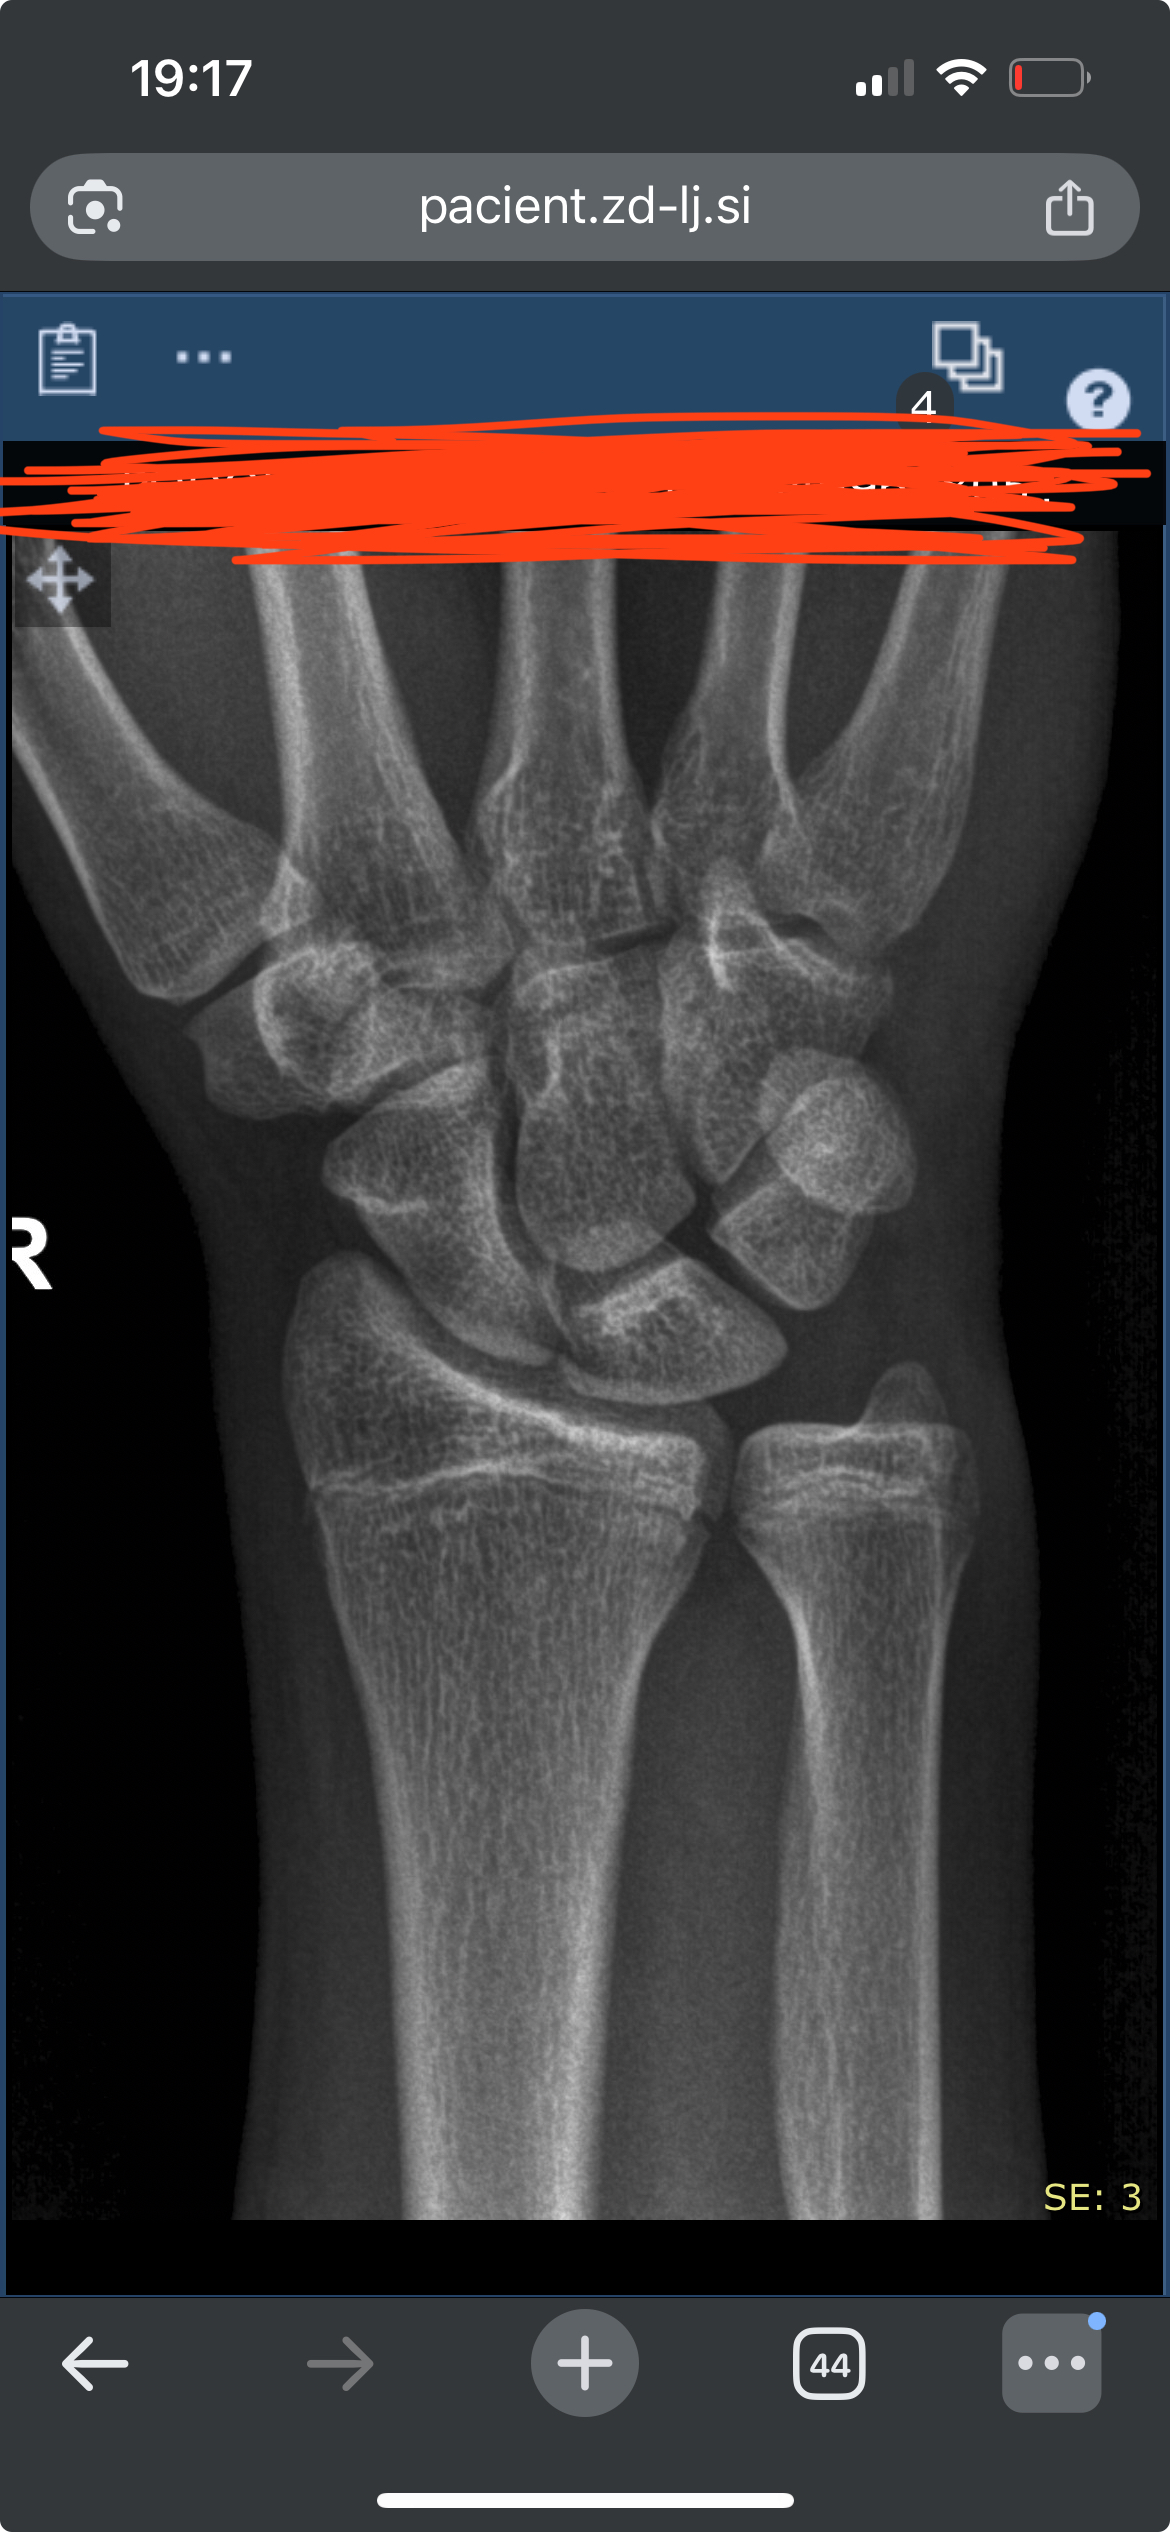

My wrist Xrays finally got here and here it is.

As far as im concerned (my doctor agrees) the plates seem fully open and operational, therefore motivating me to try to gain a few more inches. backstory: 17yo male 180cm 77kg, father 185cm.